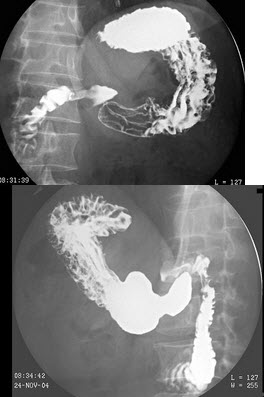

17、单项选择题

女,53岁,常感中上腹不适,结合图像,最可能的诊断为()

A.正常表现

B.慢性胃炎

C.胃溃疡

D.胃憩室

E.胃癌